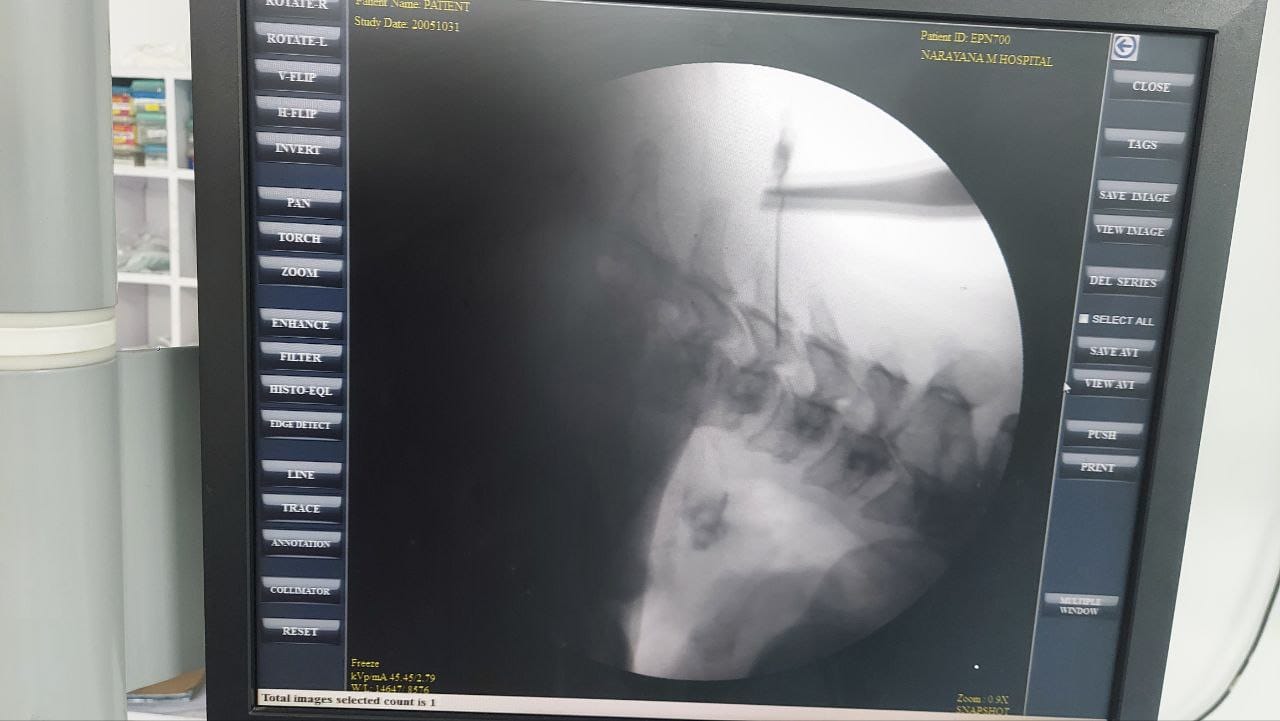

Procedures

Struggling with chronic pain? Get advanced, personalised pain management from Dr. Manish De, one of Kolkata’s leading pain specialists. From knee pain, heel pain, low back pain, frozen shoulder, migraines, cancer pain to post-TKR persistent pain—Dr. De offers safe, evidence-based treatments across multiple locations: